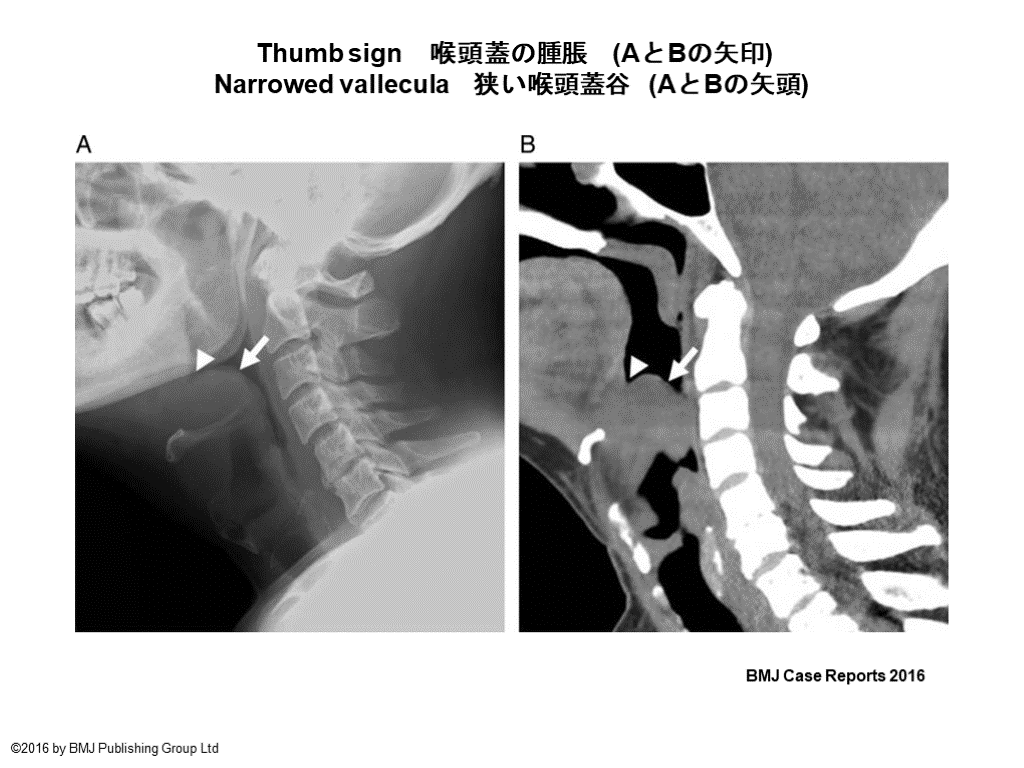

喉頭蓋炎の画像 USでの評価も試みられている J of Gen and Family Med. 2020

Thumb sign 喉頭蓋の腫脹 (AとBの矢印) Narrowed vallecula 狭い喉頭蓋谷 (AとBの矢頭) BMJ Case Reports 2016 ©2016 by BMJ Publishing Group Ltd